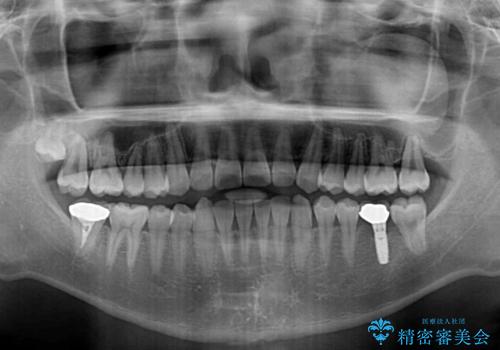

- 上顎前歯の隙間を気にして来院された患者様です。

下顎前歯に叢生がありましたが、特に気にしていらっしゃいませんでした。

下顎臼歯にインプラント補綴治療がされており、全顎治療するにはクラウンの作り替えが必要となる旨を説明し、ワイヤー装置により上顎のみの矯正治療を行うこととしました。

下顎前歯の叢生解消も提案しましたが、上顎の隙間が閉じたことで満足されました。

空隙歯列弓はマウスピースによる保定を行っても、すぐに後戻りを起こしてしまうため、ワイヤーリテーナーによる保定を併用することとしました。